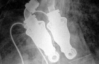

40-летнему Мэтью Грину сделали пересадку искусственного сердца в больнице Папворт Кембриджширского графства. Он может свободно подниматься по лестнице, гулять по улице и продолжать ждать пересадку настоящего сердца.

Имплантант работает с помощью портативных механических устройств.

Считается, что Мэтью Грин - первый пациент, который вернулся домой с искусственным сердцем.